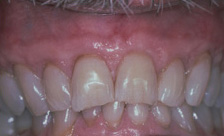

Case #1

| BEFORE | AFTER |